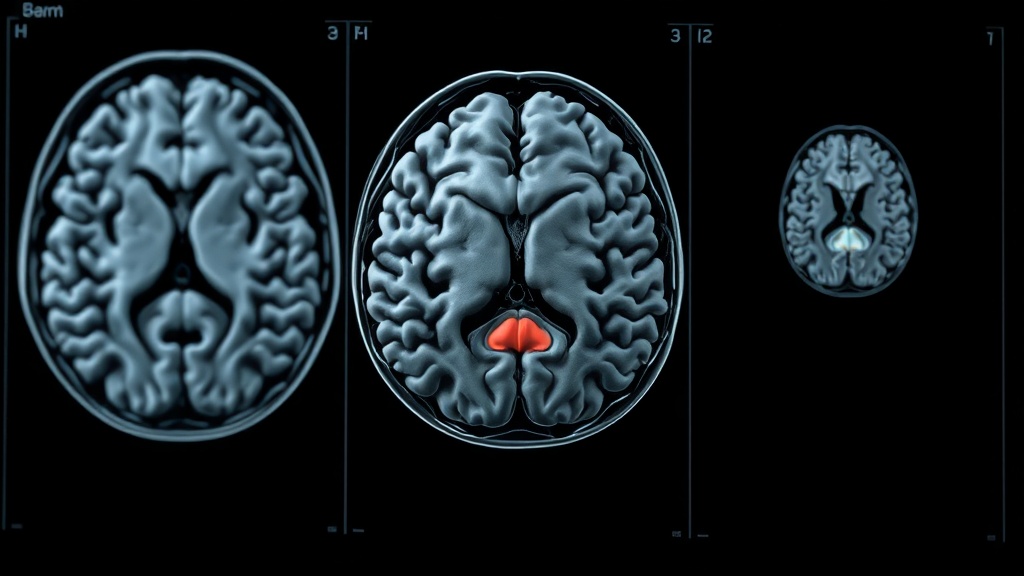

New research has detailed five distinct phases of brain development throughout human life, identifying critical turning points at ages nine, 32, 66, and 83. This comprehensive study involved brain scans of nearly 4,000 participants aged up to 90, revealing crucial insights into neural connections across different life stages.

The University of Cambridge researchers found that the brain continues to mature through adolescence until the early thirties, a period identified as the brain's peak. This understanding challenges previous assumptions about brain development timelines and highlights a prolonged period of adolescent-like brain states.

These findings hold significant implications for understanding the varying risks associated with mental health disorders and dementia throughout a person's life. By mapping these developmental stages, scientists aim to provide better context for age-related neurological conditions.